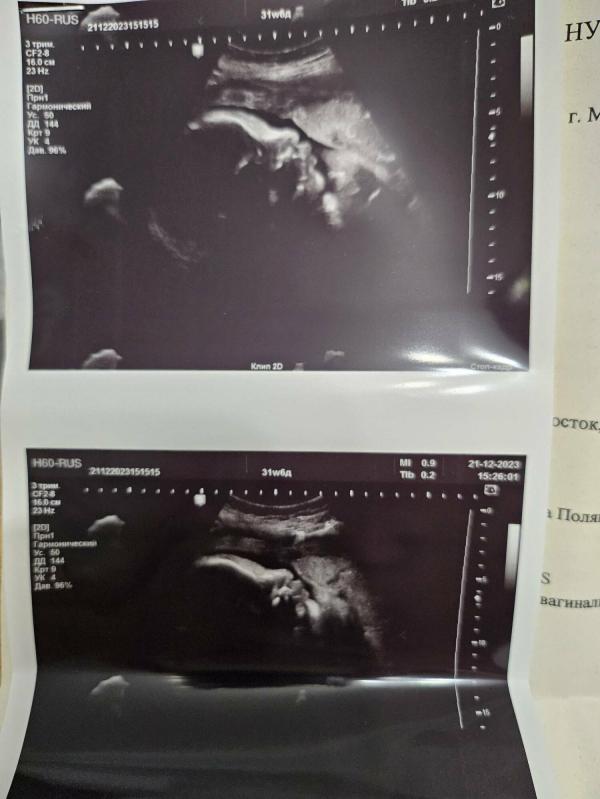

3 скрининг: как малыш сосал пальчик на УЗИ? Мой мальчик, жду встречи!

3ий скриниг.

Пока ехала на узи проголодалась, в итоге смотрели как малыш сосал свой пальчик, моя бедняжка 🥲.

Мой мальчик ❤️